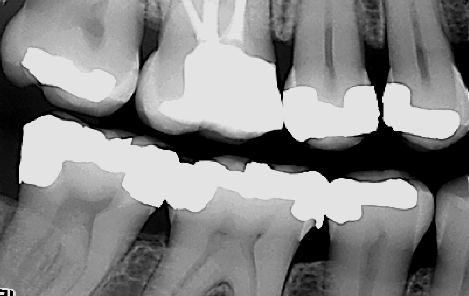

Tannlegen må vurdere behovet for å ta røntgenbilder i forbindelse med undersøkelsen. Røntgenbilder brukes for å diagnostisere sykdommer i de deler av tennene som ikke er synlige i munnen. I tillegg kan de avdekke patologi i kjevene. Eksempler på slike sykdommer kan være hull under gamle fyllinger eller kjevecyster. I tillegg kan røntgenbilder tatt over flere år sammenlignes. På denne måten kan man vurdere hvorvidt en tilstand har utviklet seg eller ikke, som for eksempel et begynnende hull.

Det finnes forskjellige former for røntgenbilder. Ved en regelmessig tannlegeundersøkelse er det vanligvis såkalte bitewings som benyttes. Bitewings gir tannlegen informasjon om blant annet hull i tennene, begynnende hull og kvaliteten til gamle fyllinger. De kan også si noe om tennenes feste og avdekke tegn til periodontitt (tannløsningsykdom). Ved behov kan bitewing-bildene suppleres med små bilder av avgrensede områder, som for eksempel bilder av tannrøtter.